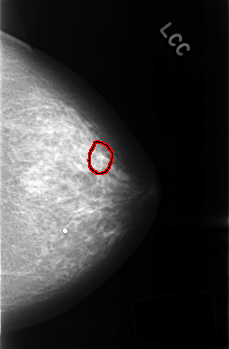

C_0434_1.LEFT_CC

LEFT_CC LINES 4528 PIXELS_PER_LINE 2976 BITS_PER_PIXEL 12 RESOLUTION 50 OVERLAY

FILE: C_0434_1.LEFT_CC.OVERLAY

TOTAL_ABNORMALITIES 1

ABNORMALITY 1

LESION_TYPE MASS SHAPE IRREGULAR MARGINS SPICULATED

ASSESSMENT 3

SUBTLETY 3

PATHOLOGY BENIGN_WITHOUT_CALLBACK

TOTAL_OUTLINES 1

BOUNDARY